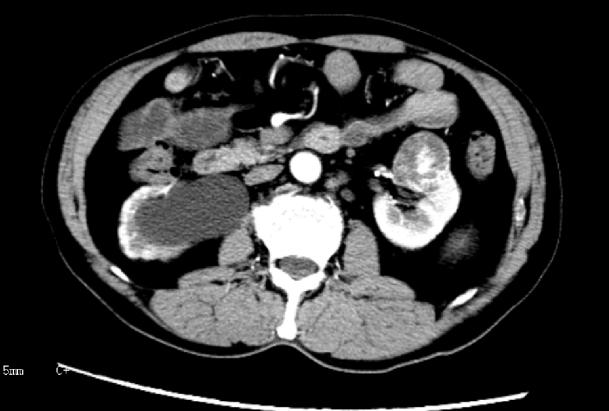

近日,捷克论坛 泌尿四科收治了这样一位年轻的肾癌患者。患者因突发右侧腰痛不适去医院检查,泌尿系CT显示右侧肾脏中度积水,右侧输尿管下段结石,同时发现左侧肾脏外缘直径约4cm占位性病变。医护团队在完善术前准备后,对其进行了右侧输尿管镜钬激光碎石取石术+左侧保留肾单位肾部分切除术手术治疗。术后,患者恢复良好。术后一月复查泌尿系CT,右肾积水完全消失,左侧肾肿瘤完整切除并有效的保留左侧肾脏功能。